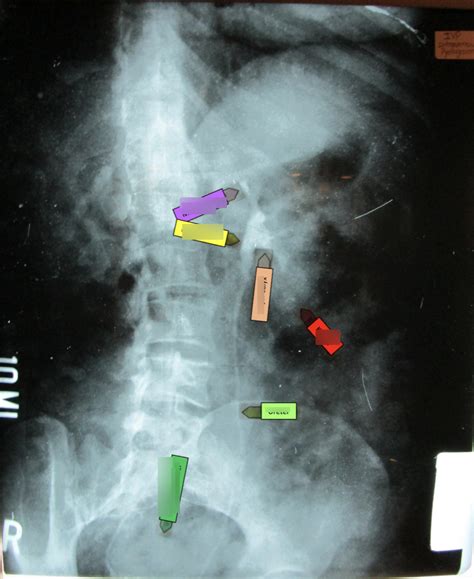

The ureters are the tubes that transport urine from the kidneys to the bladder. On an IVP, we can see the ureters’ course as they descend from the kidneys. We can assess their width and look for any blockages, such as kidney stones, or compressions. The IVP allows us to observe peristaltic movement, the wavelike contractions that propel urine down the ureters. This is super important because any obstruction in the ureters can lead to a buildup of urine, potentially causing pain and kidney damage. This visualization is essential for making a diagnosis.

Kidney stones are one of the most common findings on an IVP. The radiologist looks for opaque (white) shadows in the kidneys or ureters, which are the stones themselves. They vary in size and shape. The IVP can help determine the size, location, and number of stones. It’s super important to know this information to help guide treatment options. Depending on the size and location, kidney stones can be managed through medication, procedures like shock wave lithotripsy, or surgery. IVP allows the radiologist to evaluate the impact of a stone on the urinary system, looking for signs of obstruction, like swelling (hydronephrosis).

Obstructions in the urinary tract are another common finding on IVP. The radiologist is checking for any blockages, which can be caused by kidney stones, tumors, or other conditions. These blockages can prevent urine from flowing freely, causing pain, infection, and kidney damage. The IVP can show the location and severity of the obstruction . It might show a dilated ureter or kidney, indicating a backup of urine. The images also help the radiologist determine what is causing the obstruction. This information helps the urologist or nephrologist plan the best approach for relief.